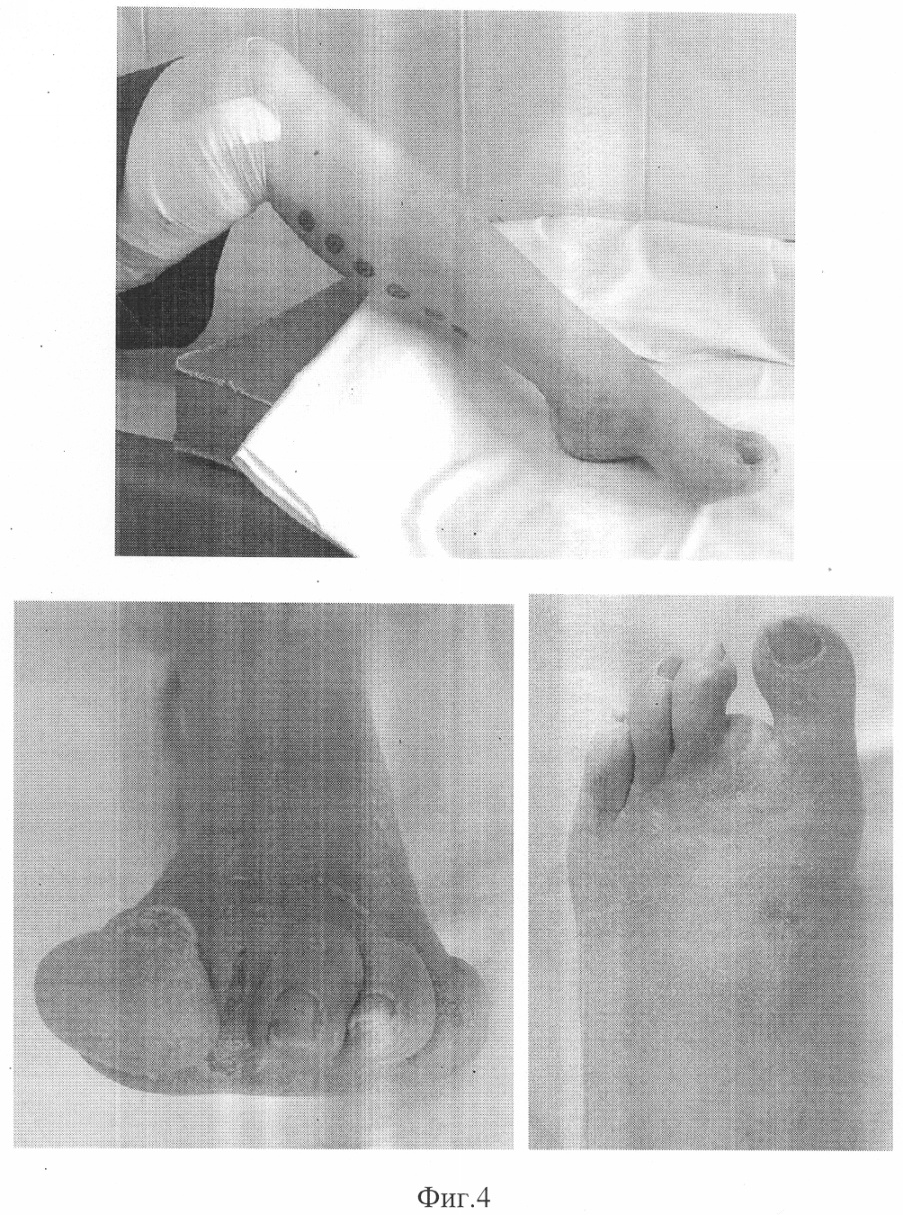

фиг.2 – фото конечности больного Н. до лечения;

фиг.4 – фото конечности больного Н. после лечения.

Больной Н. (фиг.1, 2) поступил в клинику с диагнозом: Сахарный диабет, II тип, субкомпенсация. Синдром диабетической стопы слева. Трофическая язва в области ампутированного II пальца левой стопы. Диабетическая ангиопатия. Перемежающаяся хромота через 150-200 метров. На артериограмме прослеживается локальная (4-5 см) окклюзия поверхностной бедренной артерии в средней трети, многочисленные стенотические поражения магистральных артерий на протяжении голени и стопы.

На момент выписки после проведенного лечения, общая продолжительность которого составила 23 дня, состояние оперированной конечности характеризовалось следующими данными: кожные покровы голени и стопы обычного цвета, на ощупь теплые. В области ранее имевшейся трофической язвы достигнуто ее полное заживление (фиг.4). На контрольном осмотре через 6 месяцев достигнутый результат лечения сохраняется. Трофических язв нет. Кожные покровы обычного цвета, теплые на ощупь, явления перемежающейся хромоты отсутствуют.